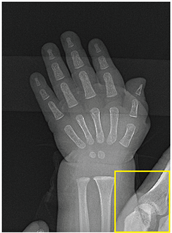

Table 2, Table 3, Table 4 and Table 5 present the results obtained through the multi-objective optimization image enhancement approach. Specifically, Table 2 and Table 3 show the results for natural images, while Table 4 and Table 5 display medical images. The tables are organized as follows: the first and second columns list the image names and their corresponding original, unenhanced versions. The third to fifth columns showcase the selected points from the Pareto front, representing the maximum contrast, knee point, and maximum detail, in that order. The final column illustrates the obtained Pareto front through the optimization process, with red, green, and orange points indicating the images that achieved maximum contrast, knee point, and maximum detail, respectively.

Table 4.

Medical image results—1.

For medical images, there are instances where differences are more perceptible. For example, in the Medical3 image, the maximum contrast solution makes it difficult to visualize the internal details of the basophil (a white blood cell highlighted in the box), which could result in a less accurate interpretation. In contrast, the knee and maximum detail solutions provide a clearer view of the interior of the white blood cell. Similarly, in the Medical5 image, the maximum contrast solution highlights the hand and arm bone structures. However, the maximum detail image offers a more precise view of the internal structures within the bones (see the highlighted region), which is crucial for a more detailed evaluation. Another notable example is the Medical8 image, where the maximum detail solution offers a more detailed view of the internal structure of the eosinophil (another type of white blood cell). However, the maximum contrast image improves the visibility of red blood cells. As shown in the yellow box, this solution reveals a red blood cell that is nearly imperceptible in the other solutions. An interesting case is the Medical6 image, where only a few non-dominated solutions are present on the Pareto front. Despite the similarities among the preferred solutions, the nodules are much more perceptible in the enhanced images than in the original image, as observed in the highlighted region.